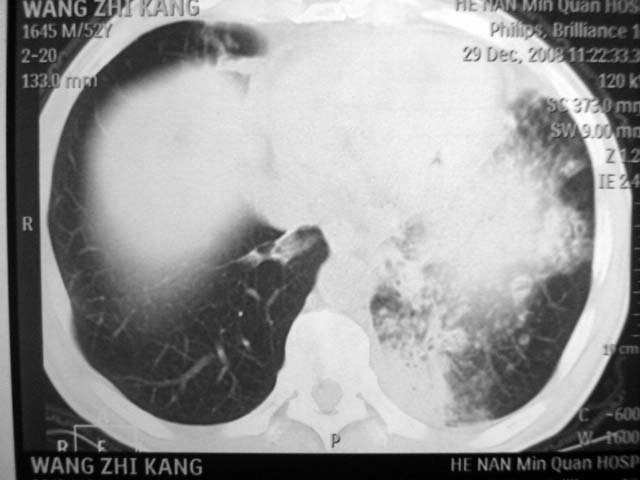

男,52岁,发热2月,糖尿病史。

抗结核治疗irpz方案,血糖未治疗,空腹15.9左右。症状无好转,左胸痛。

2、双肺见多发片状及结节状高密度影,大多数病灶中心均见“空泡征”。

3、纵隔内淋巴结肿大。

结果:两肺继发性肺结核并曲霉菌感染。